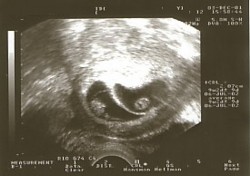

Embryon de 6 semaines

Déjà plus qu’un centimètre !

Pendant le 2e mois, le bébé prend forme: les bras apparaissent, le visage se dessine… Au début du 3e mois, il mesurera près de 4 cm !